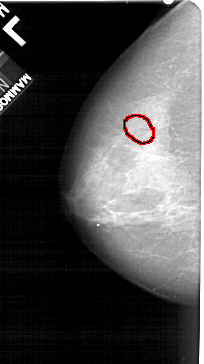

FILE: A_1316_1.LEFT_CC.OVERLAY

TOTAL_ABNORMALITIES 1

ABNORMALITY 1

LESION_TYPE CALCIFICATION TYPE PLEOMORPHIC DISTRIBUTION CLUSTERED

ASSESSMENT 4

SUBTLETY 3

PATHOLOGY BENIGN

TOTAL_OUTLINES 1

BOUNDARY